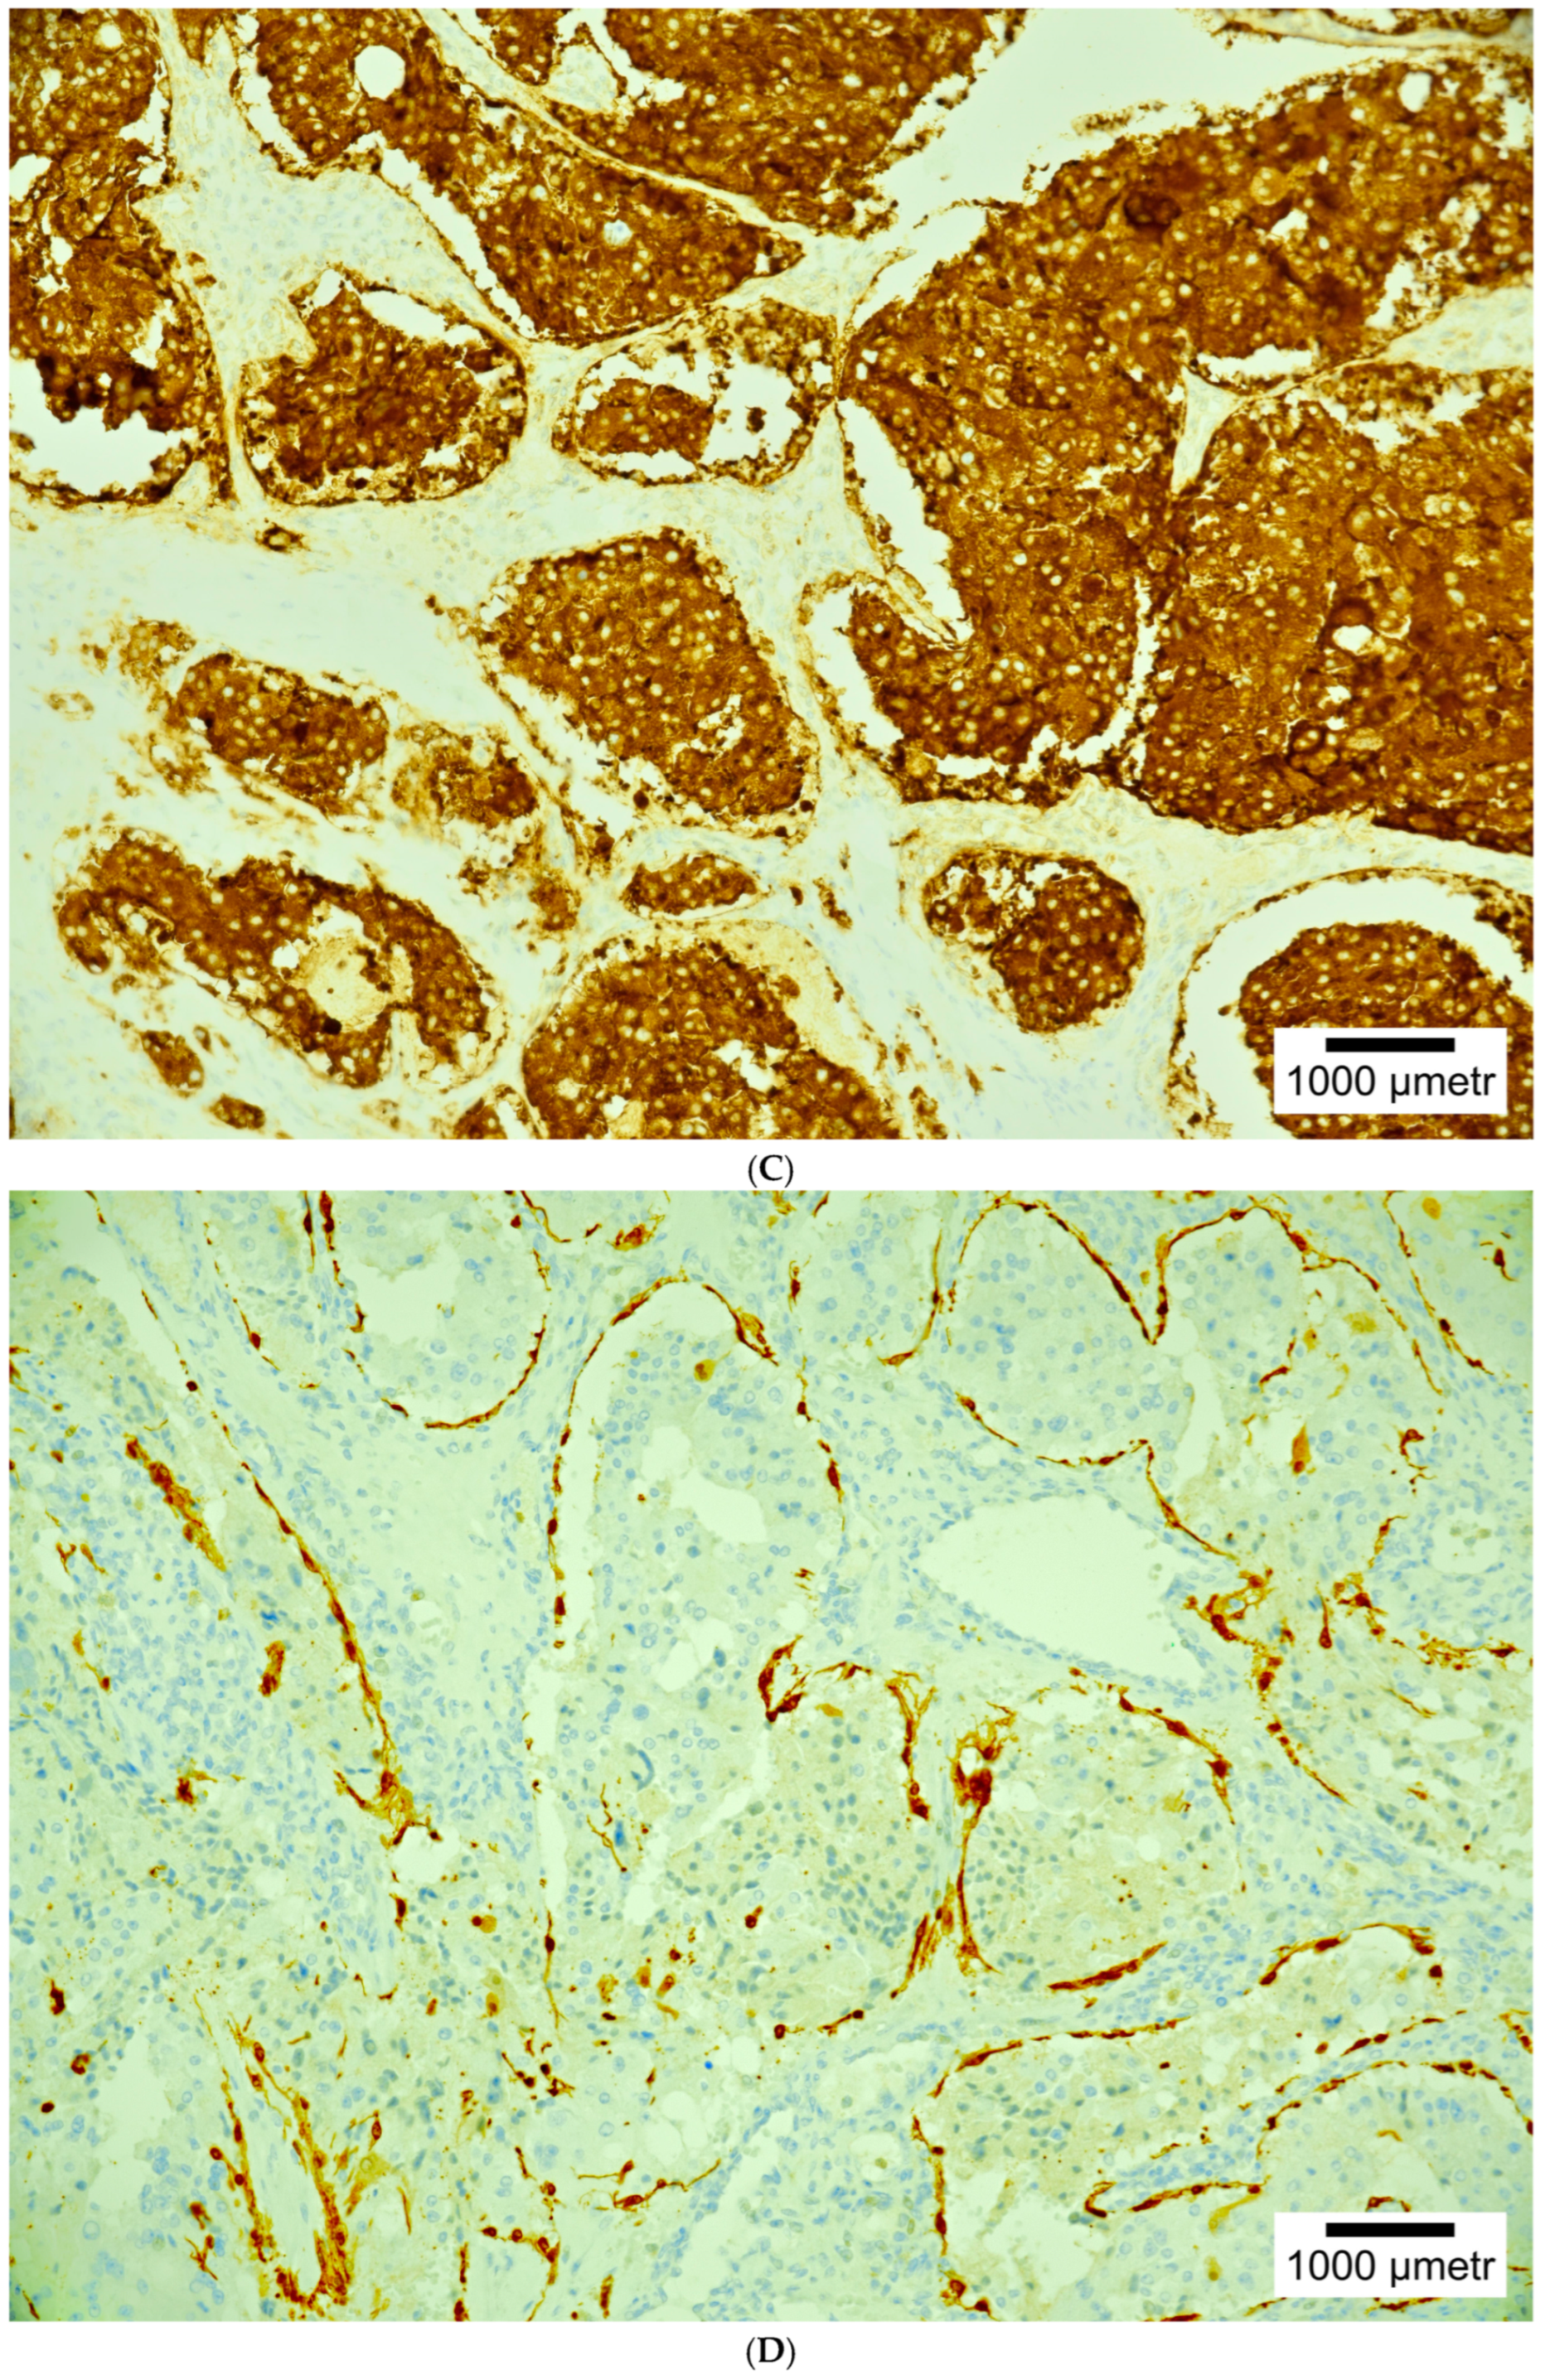

4. Histopathology